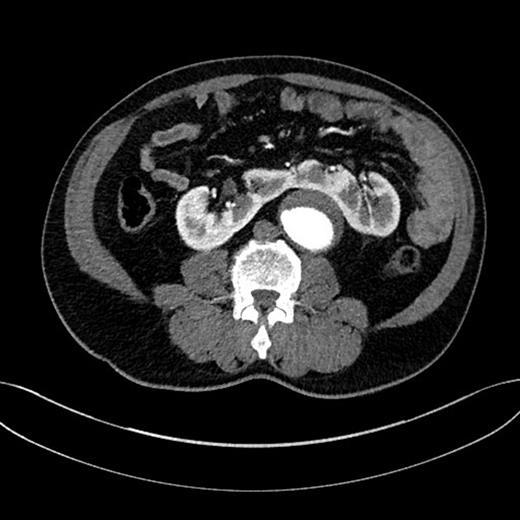

Suprarenal clamp over the left renal artery was applied for 22 min. The aneurysm was repaired using a 20 mm Dacron without the left renal artery reconstruction (the graft was sutured obliquely so that the origin of the left renal artery was patent) (Fig. 3).

The divided renal isthmus and repaired aneurysm using a 20 mm Dacron.